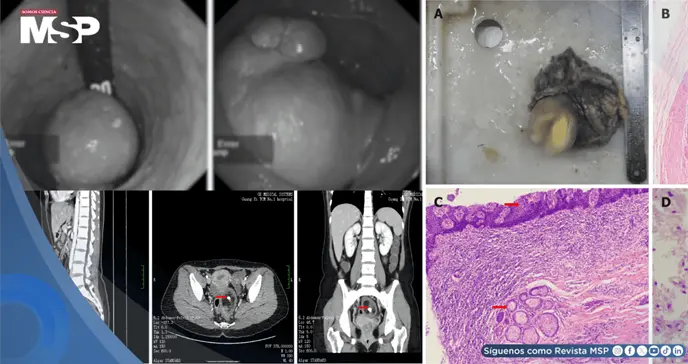

El examen reveló una masa de 4 cm × 3 cm × 3 cm dentro del ano, a unos 6 cm de la línea dentada, lisa al palparla y no dolorosa al exteriorizarse. Los análisis de laboratorio, como hemograma completo, electrolitos séricos, gonadotropina coriónica humana y panel metabólico, resultaron normales.

Sin embargo, la tomografía computarizada (TC) mostró una lesión redonda de 6,3 cm × 4,7 cm × 5,1 cm en la pelvis, con sombra escamosa de baja densidad, calcificación central, realce leve periférico y límites claros, sugestiva de teratoma; además, se observó un quiste anexial bilateral de baja densidad.

El examen patológico identificó dos tumores conectados en mucosa y serosa intestinal, de 6 cm × 5 cm × 4 cm y 2 cm × 2 cm × 2 cm, respectivamente. Microscópicamente, contenían piel con anejos, glándulas, grasa, tejido óseo, médula ósea y cerebral, confirmando un teratoma rectal maduro.

Los márgenes quirúrgicos estaban libres de tumor, y de seis ganglios linfáticos examinados, ninguno mostró metástasis (0/6).